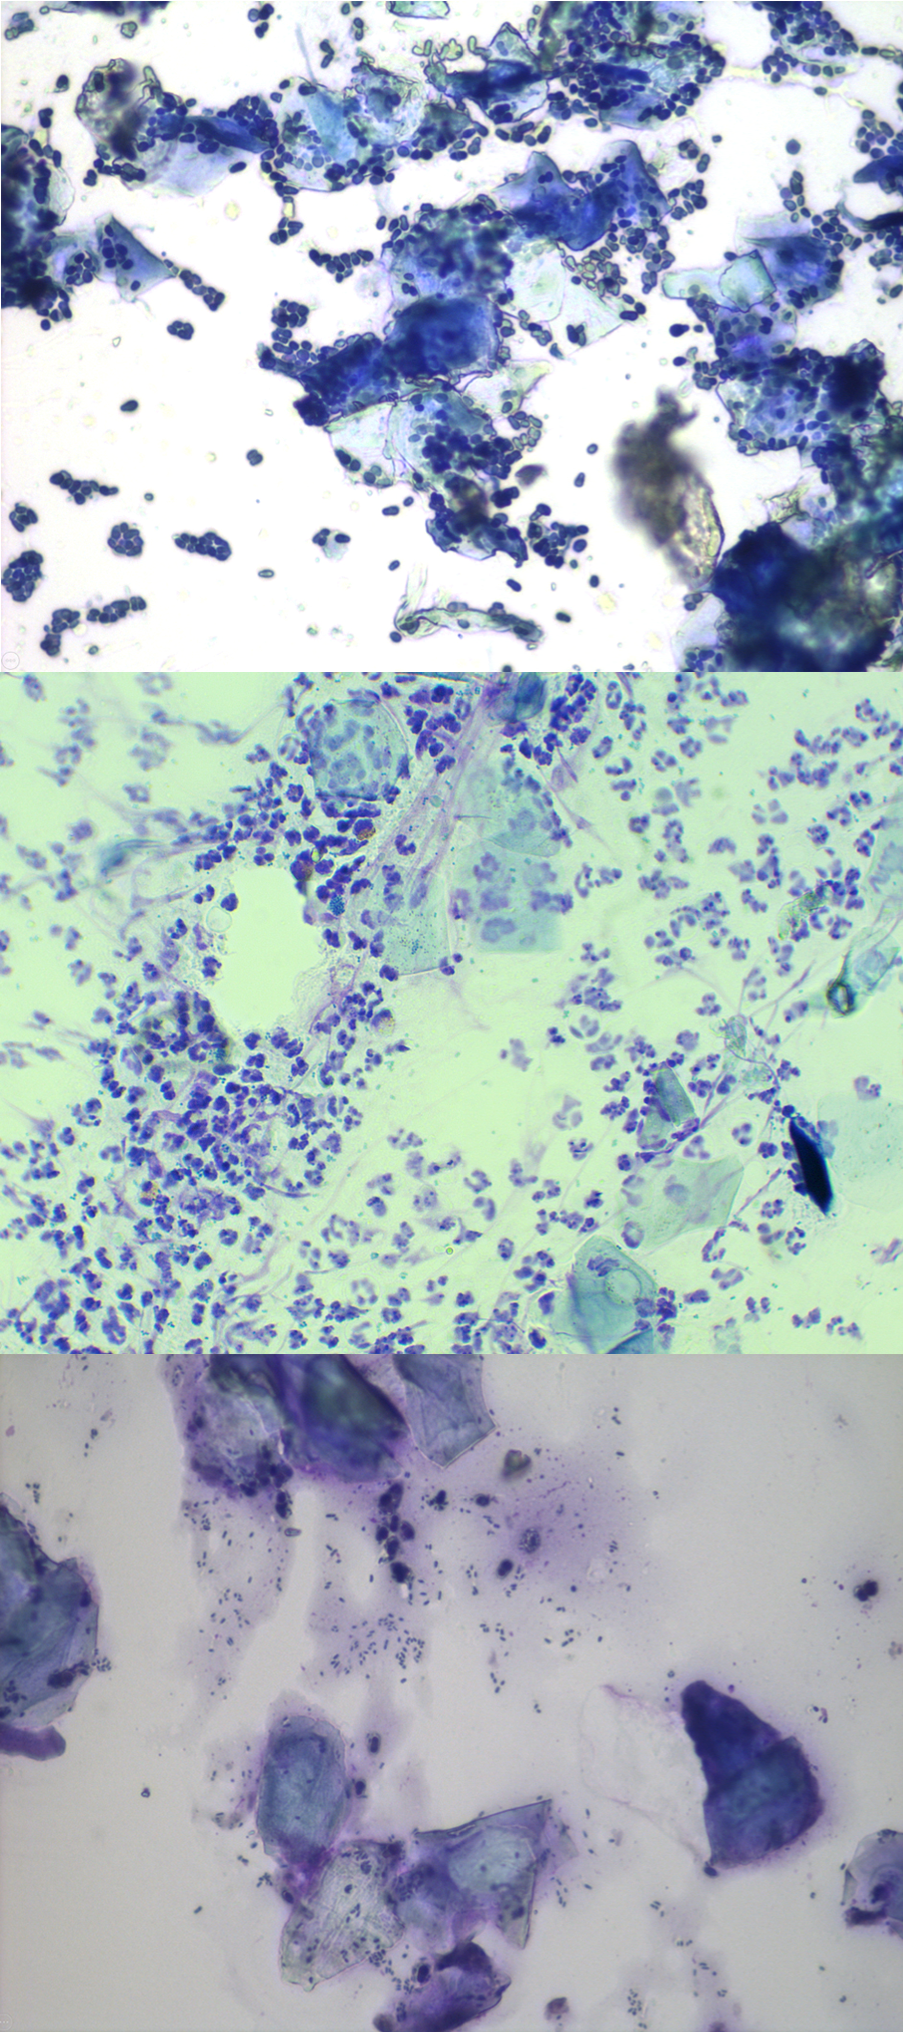

The images below display different stages and forms of ear inflammation.

Images (CWalker, ThePhotoVet)

The next highly recommended step in the investigation will be to take a sample of any debris from your dog’s ear to be studied under a microscope, a process known as cytology.

Cytology is a quick, easy to perform test which can be done within the vet practice and will help the vet to decide if there are any signs of bacterial or yeast overgrowth.

Using a cytology brush, a cotton bud or possibly a gloved finger, material is collected from your dog´s ears and placed on a glass slide. The sample is dyed with special colouring to allow your vet to investigate what is going on in your dog´s ear on a microscopical level. All to decide whether there is an overgrowth of bacteria or yeast and to look for inflammatory cells which are otherwise invisible to the human eye.

Not only does cytology allow your vet to choose an appropriate treatment, but it is also helpful to repeat it at your dog´s revisits to evaluate treatment success, if any changes to the treatment protocol are needed and to assist in developing a long-term plan for your dog´s ear problem.